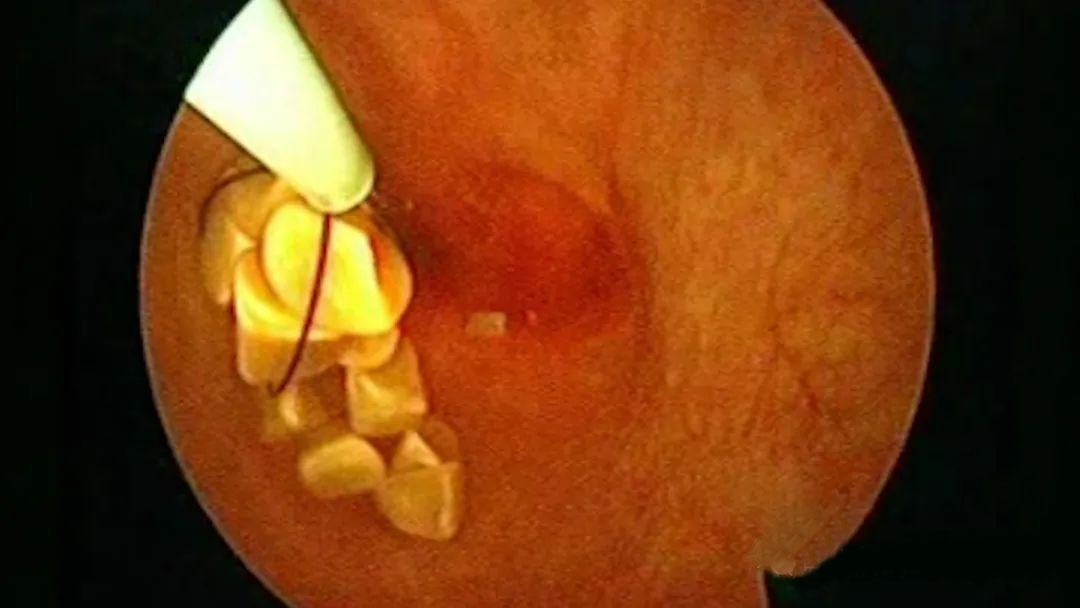

何明刚主任在专题演讲中,结合实际病例和保胆手术演示,就《保胆取石术中对胆囊粘膜上的粘液及细小胆固醇颗粒处理的体会》,围绕保胆术中处理的热点和难点,以及术中关键的细节技巧,展开了深度分享和经验总结。

▲何明刚主任保胆取石手术演示